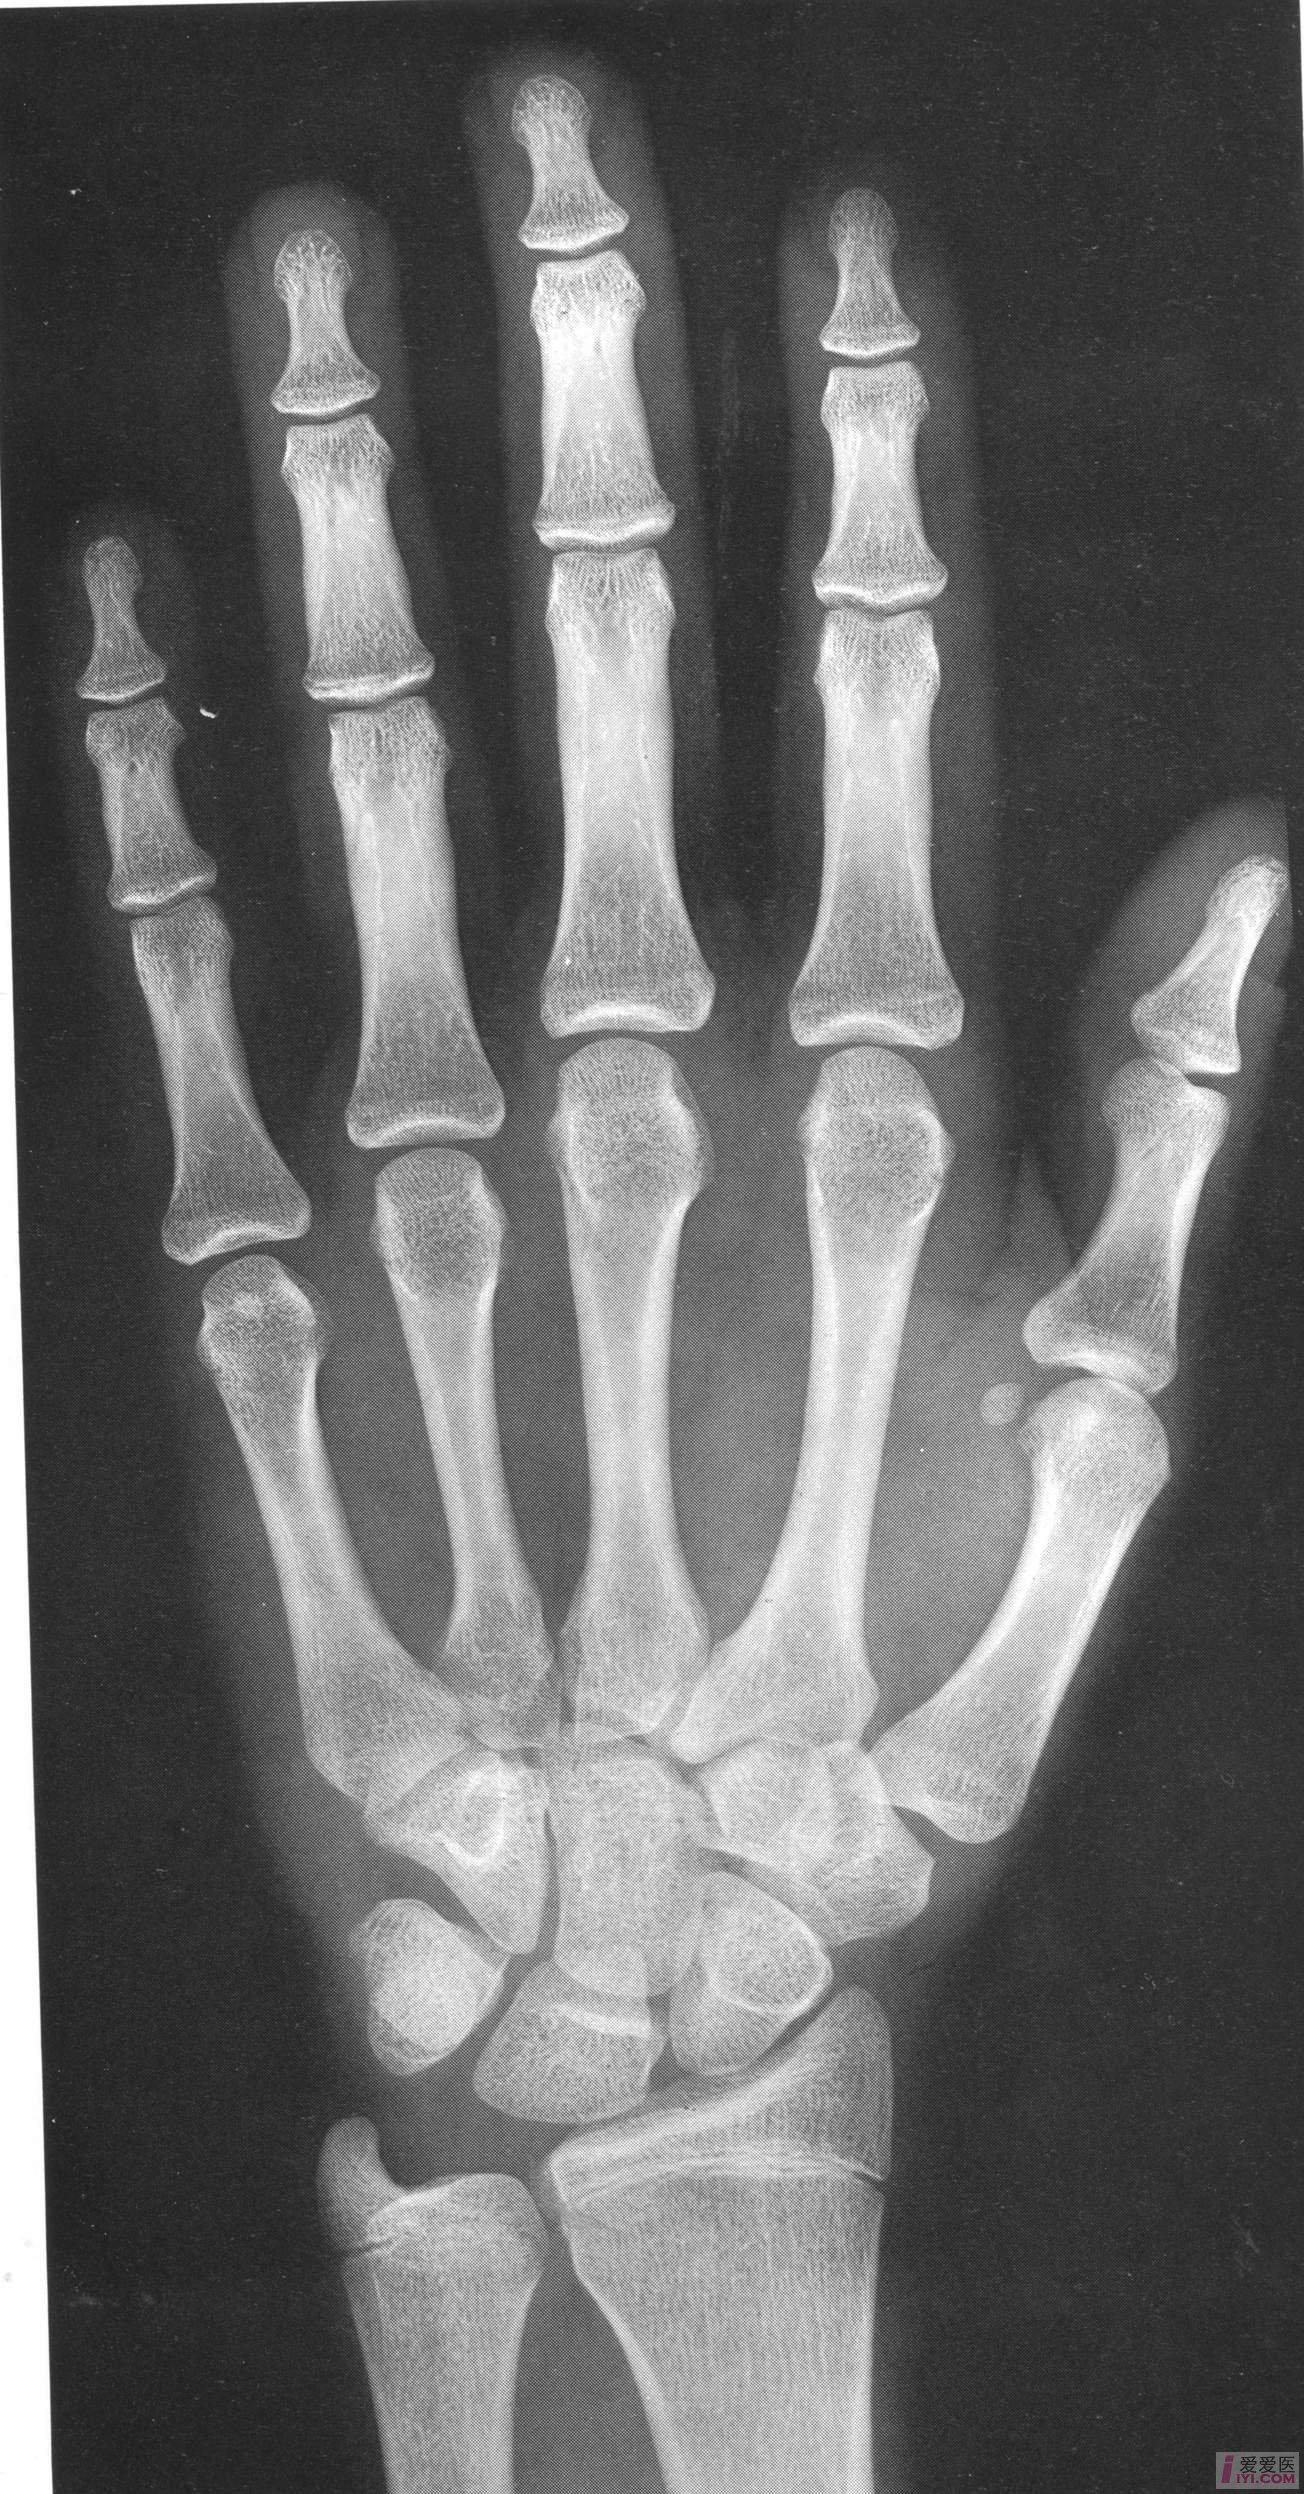

中国儿童标准骨龄片

最全骨龄图谱:男孩女孩都有